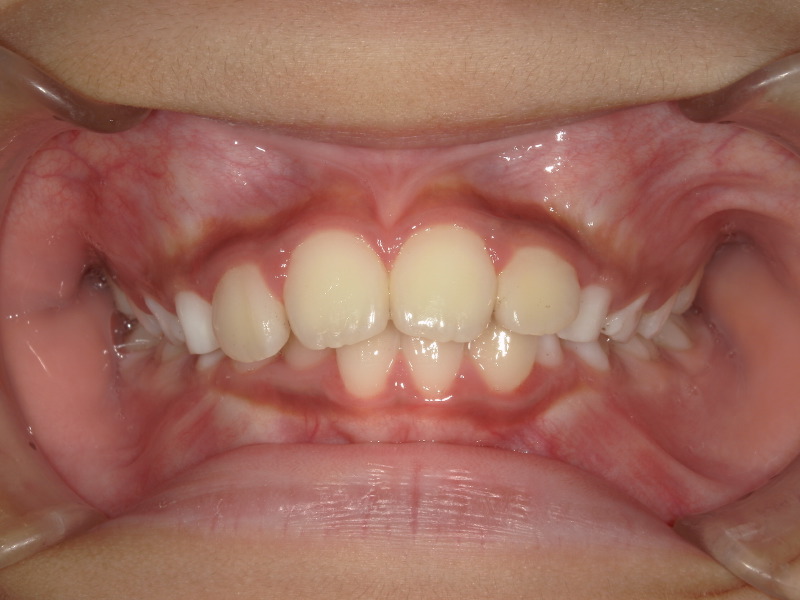

最初の検査時に撮影した写真です。

お母さんが気にされていた前歯が大きいという点ですが、歯が大きく見えるのは噛み合わせの状態や、顎の骨の成長が足りていないケースも考えられます。

下の歯が隠れており、前歯の存在が大きく感じます。

下の歯並びは2番目の歯が後ろから生えてきており、スペースが足りないようでした。